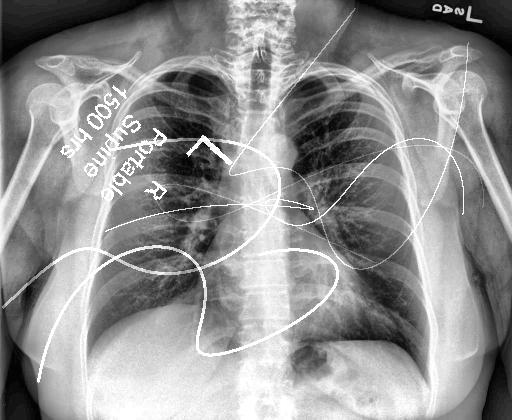

Automated catheter detection is a challenging task. Although most catheters have a radiopaque strip to facilitate detection, the strip may become less apparent depending on the projection angle. Catheters maybe confused by other similar linear structures like ECG leads and anatomy including ribs. Additionally, portions of catheters can be occluded by anatomical structures given that radiographs are a 2D projection of a 3D structure. For example, when a NGT is placed within the oesophagus, the catheter itself becomes less apparent due to the high density of the adjacent vertebrae. Finally, the number and type of catheters that could possibly appear in pediatric X-rays are unknown a priori. The catheters may be intertwined with each other thus making simple line tracing methods fail. Figure 1 gives three sample pediatric X-ray images with some common catheters highlighted in different colors.

To alleviate this annotation problem in catheter detection, we proposed to use X-ray images with simulated catheters by exploiting the fact that catheters are essentially tubular objects with various cross sectional profiles. To be more specific, a synthetic 2D projection of a catheter is generated by first simulating a horizontal catheter profile and then using it as a brush tip to draw along a B-spline path. This generated catheter is then composited with an X-ray image serving as the training data. Another contribution of this work is a segmentation network that can inherently take into account multi-scale information. This network adopts a UNet-style form and contains a recurrent module that can process inputs with increasing scales111Our code is available at https://github.com/xinario/catheter_detection.git.. We have empirically shown that by iterating through the scale space of the input image, higher recall is achieved as compared to using a single scale. Details about the methods are discussed in Section 3. Three sample detection results are shown in Figure 1.

The test dataset is collected locally and only contains frontal chest-abdominal X-rays from patients < 4 weeks old. This is the most common radiograph obtained to confirm placement of catheters such as UACs and UVCs in neonates. Currently, the test set has 35 fully labeled images with different catheter types with sample images previously shown in Figure 1. All the annotated catheters (lines excluding ECG leads) are treated as the same class in the detection.

Qualitative visual examples of the raw catheter likelihood maps obtained directly from the network without any postprocessing are shown in Figure 5. It can be seen that the proposed network at the highest scale (scale 3) achieves the best visual appearance as compared to the other methods. The maps from the proposed network at scale 2 and scale 3 look much cleaner than w/oR and fcn8s. We would attribute this to the iterative refinement of the detection results by using the recurrent module. When comparing results from the proposed network at different scales, we can see that the likelihood map from the smallest scale contains almost all line-like structures, including not only catheters but also ribs and ECG leads. This is because catheters, ribs, ECG leads look similar at a smaller scale. These irrelevant line-like structures are gradually filtered out in higher scales because catheters, especially UVCs and UACs, begin to appear as two parallel edges whereas ribs and ECG leads continue to appear as a single solid line.

There are certain situations where our proposed method would fail. Figure 7 (a) and (b) show a partially detected NGT. This mostly likely resulted from the decreased visibility of the radiopaque strip. Figure 7 (a) also shows another failure situation where the inferior portion of the UVC is occluded by the abdomen. (c) shows the case of a falsely detected unidentified line and (d) shows part of the lateral aspect of the rib cage falsely identified as a catheter.